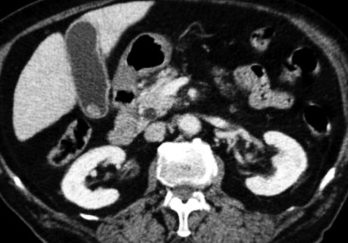

Abdominal CT scan. Hemorrhagic rupture of a simple hepatic cyst without active hemorrhage. The presence of free intraperitoneal fluid is noted (Courtesy Dr. V. Penopoulos)